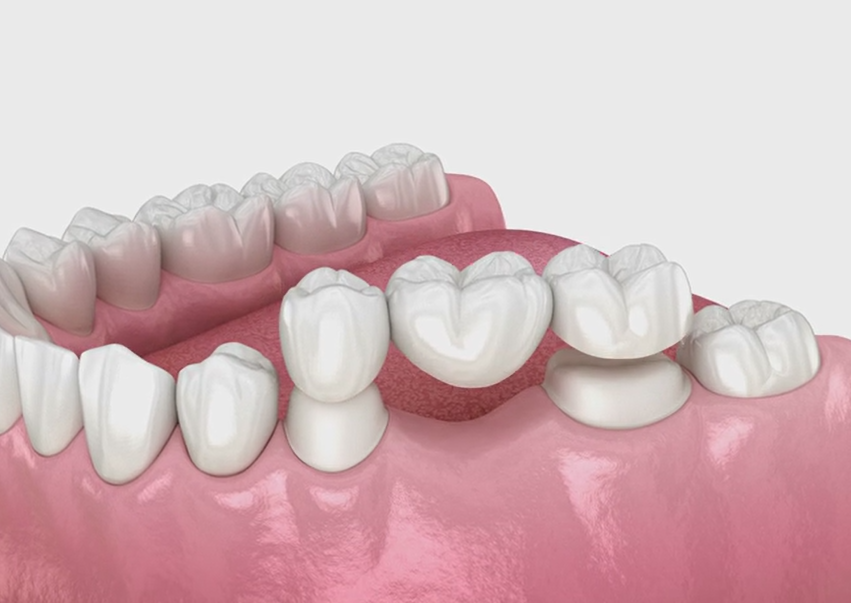

When there is a gap created by one or more missing teeth, bridges are attached to the adjoining natural teeth to fill the gap. Bridges work best for those who have only a few missing teeth. With a fixed bridge, the artificial tooth (known as a pontic) is anchored to new crowns attached to the teeth on both sides of the gap.

It requires two to three visits to complete the treatment.

1. Missing one tooth

2. Reshaping adjacent tooth

3. Reshaping adjacent tooth

4. Bridge is cemented